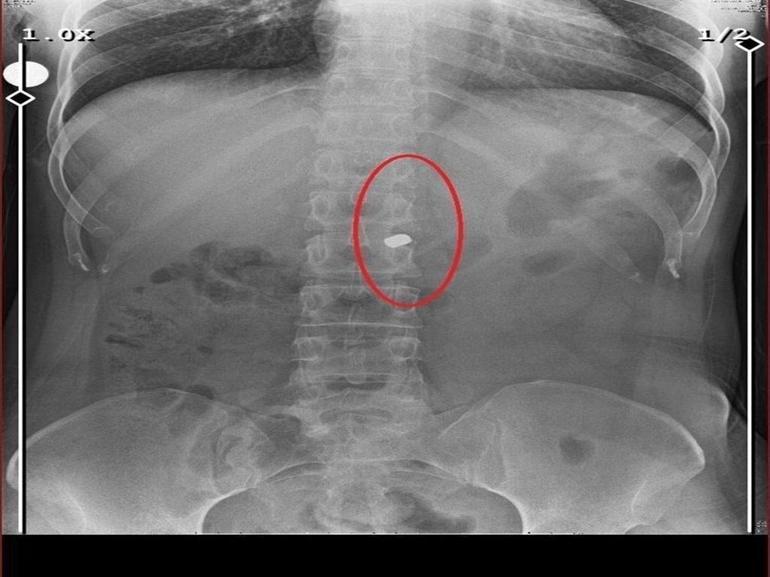

İlyas Sarıkaya, sevgilisi Fatma O.'yu da 8 kurşunla vurup, yaraladı. Arkadaşı Özaslan'ın cesedini önce çarşafa sonra da streç filme sarıp bantlayan Sarıkaya, eczaneden aldığı sargı bezi ve ilaçlarla pansumanını yaptığı sevgilisine yaralı haldeyken 21 gün boyunca cinsel saldırıda bulundu.

Fatma O., annesine yazdığı mesajda, “Odada ceset var. Telefon dinleniyor. Bana 8 el ateş etti. Yaralıyım. Polisi görürse önce beni öldürecek. Onu parayla kandırıp, evden çıkartın. Sonra da beni alın” dedi. Fatma O.’nun annesi, bu mesaj sonrası polise gidip şikayette bulundu. Polis, Fatma O.'nun annesi aracılığıyla Sarıkaya ile iletişime geçti. Fatma O.'nun annesi, telefonla aradığı Sarıkaya'yı, kızına para götürmesi için evine çağırdı. Ekipler, parayı almaya gelen Sarıkaya'yı kendilerine silah çekmesine rağmen yakaladı. Eve giden ekipler, ağır yaralı haldeki Fatma O. ve kokmaya başlayan cesetle karşılaştı. Emniyetteki işlemlerin ardından Sarıkaya tutuklanıp, hakkında dava açıldı.